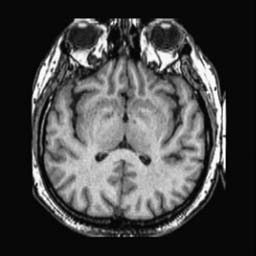

To demonstrate the effectiveness and efficiency of the proposed image fusion method , we conduct a set of comparative experiments on three image datasets. The first is composed by 8 pairs of multi-modal medical images and the second one contains 15 pairs of multi-focus gray or color natural images. These two datasets are often used in many related papers and some examples are shown in Figure 3(a) and Figure 3(b). The third one is a new multi-focus cervical cell image dataset collected by ourselves, which consists of 15 groups of color images and each group contains a series of multi-focus cervix cell images with size of or , etc. Some source examples are shown in Figure 3(c). Our source code implemented in C++ along with the new multi-focus cervical cell image dataset is available online.

We first evaluate the performance of the proposed method under varying total number of octaves and number of layers sampled per octave. The fused images of a pair of multi-modal medical images with different and are shown in Figure 4. In this example, on the one hand, when only 1 or 2 octaves are involved in constructing the DoG pyramid, the fused images fail to keep the integrity information of large size objects (e.g. eyeballs), while by increasing the value of , the integrity information of eyeballs is preserved. On the other hand, although not as significant as the increase of octave numbers , the fused image can contain more details by the increase of layer numbers . The corresponding objective quality metrics are shown in Figure 5. As shown in Figure 5(a), most of the metric values are improved as the number of octaves increases with the fixed layer numbers 3 in the global tendency and each of them tends to be stable when the number of octaves is 5. To get a relatively good quality from Figure 5(b), we can notice that some of the metric values can get a good performance when the number of layers is 3, such as the MI, SSIM, QI and VIF, though there are only a little change of all the metric values by increasing the number of layers with the fixed octave numbers 5. Because it will result in more computation burden with the increase of the value and , and for different kinds of source images, there are different performance with the diverse parameter settings. To get a trade-off between them in our experiments, we set for the multi-modal dataset, for the natural datasets and for the multi-focus cell dataset, respectively.

Figure 6 shows the fused images obtained by different methods with the multi-modal source images shown in Figure 3(a). As shown in these figures, the proposed method can produce images which preserve the complementary information of different source images well. Moreover, due to the scale-invariant structure saliency selection, our method can keep the integrity information of large size objects and the visual details simultaneously. Although the fused image generated by other methods can also capture the details to some extent, all of them fail to keep the integrity information of large size objects such as the eyeballs. Furthermore, from Figure 6(k)-6(t), the DTCWT, GFF, IM and NSCT methods may decrease the brightness and contrast while the proposed method can preserve these features and details without producing visible artifacts and brightness distortions.